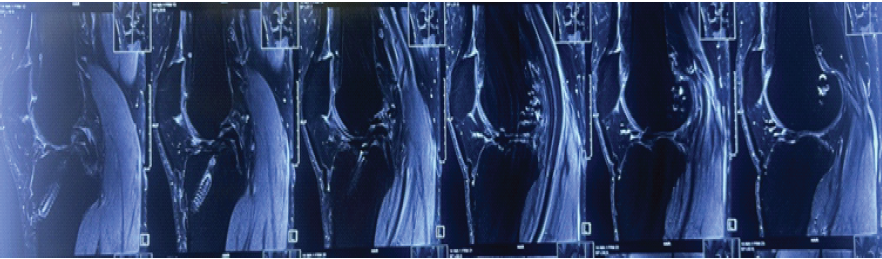

A 31-year-old male sustained a twisting injury to his left knee following a mis-landing of a flip while landing on a trampoline. The patient reported immediate pain, joint locking, and inability to fully extend the knee. The patient had a history of ACL reconstruction performed a year ago at another center. Physical examination revealed medial and lateral joint line tenderness, a positive McMurray test, and a fixed flexion deformity of 10°. Stability testing revealed negative Lachman and Anterior Drawer tests. Distal neurovascular deficits were ruled out. Plain knee radiography showed no abnormality in the bone structure. Sagittal sections of magnetic resonance imaging (MRI) revealed displaced bucket-handle tears involving both the medial and lateral menisci, exhibiting the classical “Double PCL” sign (Fig. 1).

Figure 1: Double posterior cruciate ligament sign indicative of bucket handle medial meniscus tear.